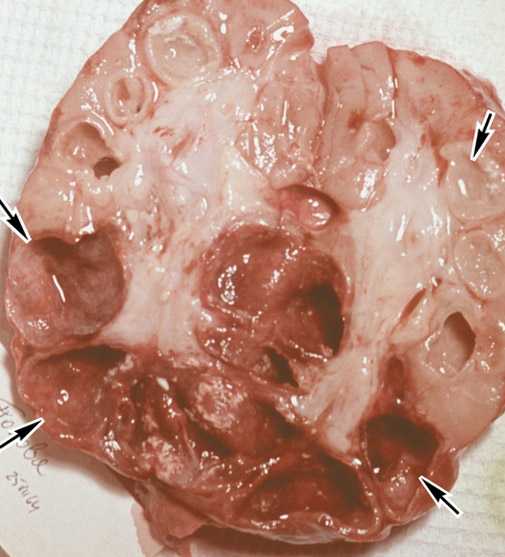

ΠΠ΅ΡΠ²ΠΎΠ½Π°ΡΠ°Π»ΡΠ½ΠΎ, ΠΏΠΎΠΏΠ°Π΄Π°Ρ Π² ΠΎΡΠ³Π°Π½Ρ Π΄ΡΡ Π°Π½ΠΈΡ ΡΠ΅Π»ΠΎΠ²Π΅ΠΊΠ°, ΠΌΠΈΠΊΠΎΠ±Π°ΠΊΡΠ΅ΡΠΈΡ Π»ΠΎΠΊΠ°Π»ΠΈΠ·ΡΠ΅ΡΡΡ Π² Π΅Π³ΠΎ Π»ΠΈΠΌΡΠ°ΡΠΈΡΠ΅ΡΠΊΠΎΠΉ ΡΠΈΡΡΠ΅ΠΌΠ΅, ΡΠ°Π·Π²ΠΈΠ²Π°ΡΡΡΡ ΠΏΠ΅ΡΠ²ΠΈΡΠ½ΡΠ΅ ΡΠΎΡΠΌΡ ΡΡΠ±Π΅ΡΠΊΡΠ»Π΅Π·Π° Ρ Π²Π·ΡΠΎΡΠ»ΡΡ . ΠΠ°Π»Π΅Π΅, Π΅ΡΠ»ΠΈ Π½Π° ΠΏΠΎΠΌΠΎΡΡ ΠΎΡΠ³Π°Π½ΠΈΠ·ΠΌΡ Π½Π΅ ΠΏΡΠΈΡ ΠΎΠ΄ΠΈΡ Π°Π΄Π΅ΠΊΠ²Π°ΡΠ½ΠΎΠ΅ Π»Π΅ΡΠ΅Π½ΠΈΠ΅, ΡΡΠ±Π΅ΡΠΊΡΠ»Π΅Π·Π½ΡΠΉ ΠΏΡΠΎΡΠ΅ΡΡ ΠΏΡΠΎΠ³ΡΠ΅ΡΡΠΈΡΡΠ΅Ρ. ΠΠ΅ΡΠ²ΠΎΠ½Π°ΡΠ°Π»ΡΠ½ΠΎ Π³Π΅Π½Π΅ΡΠ°Π»ΠΈΠ·Π°ΡΠΈΡ ΠΏΡΠΎΡΠ΅ΡΡΠ° ΠΏΡΠΎΠΈΡΡ ΠΎΠ΄ΠΈΡ Π»ΠΈΠΌΡΠΎΠ³Π΅Π½Π½ΠΎ, Π° ΠΏΠΎΡΠ»Π΅ ΠΎΠ±ΡΠ°Π·ΠΎΠ²Π°Π½ΠΈΡ ΡΡΠ°ΡΡΠΊΠΎΠ² ΠΊΠ°Π·Π΅ΠΎΠ·Π½ΠΎΠ³ΠΎ Π½Π΅ΠΊΡΠΎΠ·Π° (ΠΊΠ°Π²Π΅ΡΠ½), Π²ΠΎΠ·ΠΌΠΎΠΆΠ΅Π½ ΠΏΡΠΎΡΡΠ² ΠΏΠ°Π»ΠΎΡΠ΅ΠΊ ΠΠΎΡ Π° Π² ΠΊΡΠΎΠ²ΡΠ½ΠΎΠ΅ ΡΡΡΠ»ΠΎ ΠΈ ΠΊ ΡΠΆΠ΅ ΠΈΠΌΠ΅ΡΡΠΈΠΌΡΡ ΡΠΎΡΠΌΠ°ΠΌ Π»Π΅Π³ΠΎΡΠ½ΠΎΠ³ΠΎ ΡΡΠ±Π΅ΡΠΊΡΠ»Π΅Π·Π° Π΄ΠΎΠ±Π°Π²Π»ΡΠ΅ΡΡΡ ΠΏΠΎΡΠ°ΠΆΠ΅Π½ΠΈΠ΅ Π΄ΡΡΠ³ΠΈΡ ΠΎΡΠ³Π°Π½ΠΎΠ².

Π‘ ΠΎΠ±ΡΠ°Π·ΠΎΠ²Π°Π½ΠΈΠ΅ΠΌ ΠΊΠ°Π²Π΅ΡΠ½ Π² Π»Π΅Π³ΠΊΠΈΡ ΡΡΠ±Π΅ΡΠΊΡΠ»Π΅Π· Ρ Π²Π·ΡΠΎΡΠ»ΡΡ ΠΏΠ΅ΡΠ΅ΡΡΠ°Π΅Ρ Π±ΡΡΡ Π·Π°ΠΊΡΡΡΠΎΠΉ ΡΠΎΡΠΌΠΎΠΉ Ρ.ΠΊ. ΠΏΠ°Π»ΠΎΡΠΊΠΈ ΠΠΎΡ Π° ΡΠ΅ΡΠ΅Π· Π±ΡΠΎΠ½Ρ ΠΈΠ°Π»ΡΠ½ΠΎΠ΅ Π΄Π΅ΡΠ΅Π²ΠΎ Π½Π°ΡΠΈΠ½Π°ΡΡ Ρ ΠΌΠΎΠΊΡΠΎΡΠΎΠΉ ΠΏΡΠΈ ΠΊΠ°ΡΠ»Π΅ ΠΈ ΡΠΈΡ Π°Π½ΠΈΠΈ Π²ΡΠ΄Π΅Π»ΡΡΡΡΡ Π² ΠΎΠΊΡΡΠΆΠ°ΡΡΡΡ ΡΡΠ΅Π΄Ρ. Π‘ ΡΡΠΎΠ³ΠΎ ΠΌΠΎΠΌΠ΅Π½ΡΠ° ΡΠ΅Π»ΠΎΠ²Π΅ΠΊ ΡΡΠ°Π½ΠΎΠ²ΠΈΡΡΡ Π±Π°ΠΊΡΠ΅ΡΠΈΠΎΠ²ΡΠ΄Π΅Π»ΠΈΡΠ΅Π»Π΅ΠΌ ΠΈ ΠΊΡΠ°ΠΉΠ½Π΅ ΠΎΠΏΠ°ΡΠ½ΡΠΌ Π΄Π»Ρ ΡΠ²ΠΎΠ΅Π³ΠΎ ΠΎΠΊΡΡΠΆΠ΅Π½ΠΈΡ.

- ΠΠ°Π²Π΅ΡΠ½ΠΎΠ·Π½ΡΠΉ ΡΡΠ±Π΅ΡΠΊΡΠ»Π΅Π· β ΠΏΠΎΠ·Π΄Π½ΡΡ ΡΡΠ°Π΄ΠΈΡ, ΠΊΠΎΡΠΎΡΠ°Ρ Ρ Π°ΡΠ°ΠΊΡΠ΅ΡΠ½Π° ΡΠΎΡΠΌΠΈΡΠΎΠ²Π°Π½ΠΈΡ ΠΏΠΎΠ»ΠΎΡΡΠ΅ΠΉ ΡΠ°ΡΠΏΠ°Π΄Π°. Π‘ΠΎΠΎΡΠ²Π΅ΡΡΡΠ²Π΅Π½Π½ΠΎ ΠΊΠ°ΡΠ΅Π»Ρ ΠΏΡΠΎΠ΄ΡΠΊΡΠΈΠ²Π½ΡΠΉ, ΠΌΠΈΠΊΠΎΠ±Π°ΠΊΡΠ΅ΡΠΈΡ Π²ΡΠ΄Π΅Π»ΡΠ΅ΡΡΡ, ΠΏΡΠΈΡΠΎΠ΅Π΄ΠΈΠ½ΡΡΡΡΡ ΠΈ ΠΏΠΎΠ·Π΄Π½ΠΈΠ΅ ΡΠΈΠΌΠΏΡΠΎΠΌΡ β ΠΊΡΠΎΠ²ΠΎΡ Π°ΡΠΊΠ°Π½ΡΠ΅, ΠΎΠ΄ΡΡΠΊΠ°, Π±ΠΎΠ»ΠΈ Π² Π³ΡΡΠ΄ΠΈ ΠΏΡΠΈ Π²Π΄ΠΎΡ Π΅ ΠΈ ΠΊΠ°ΡΠ»Π΅.

- ΠΠ°Π·Π΅ΠΎΠ·Π½Π°Ρ ΠΏΠ½Π΅Π²ΠΌΠΎΠ½ΠΈΡΒ β Π΄Π°Π½Π½Π°Ρ ΡΠΎΡΠΌΠ° Ρ Π°ΡΠ°ΠΊΡΠ΅ΡΠΈΠ·ΡΠ΅ΡΡΡ Π±ΠΎΠ»ΡΡΠΈΠΌ ΠΊΠΎΠ»ΠΈΡΠ΅ΡΡΠ²ΠΎΠΌ ΠΏΠΎΠ»ΠΎΡΡΠ΅ΠΉ ΠΏΠΎΡΠ»Π΅ ΠΊΠ°Π·Π΅ΠΎΠ·Π½ΠΎ-Π½Π΅ΠΊΡΠΎΡΠΈΡΠ΅ΡΠΊΠΎΠ³ΠΎ ΡΠ°ΡΠΏΠ°Π΄Π° ΡΠΊΠ°Π½ΠΈ Π»Π΅Π³ΠΊΠΈΡ . Π£ Π±ΠΎΠ»ΡΠ½ΠΎΠ³ΠΎ ΡΠ΅ΠΌΠΏΠ΅ΡΠ°ΡΡΡΠ°, ΡΠ»Π°Π±ΠΎΡΡΡ, ΠΏΠΎΡΠ»ΠΈΠ²ΠΎΡΡΡ, ΠΊΠ°ΡΠ΅Π»Ρ Ρ ΠΎΠ±ΠΈΠ»ΡΠ½ΡΠΌ ΠΊΠΎΠ»ΠΈΡΠ΅ΡΡΠ²ΠΎΠΌ ΠΌΠΎΠΊΡΠΎΡΡ, Π²ΡΠ΄Π΅Π»Π΅Π½ΠΈΠ΅ ΠΏΠ°Π»ΠΎΡΠΊΠΈ ΠΠΎΡ Π°. Π’Π°ΠΊ ΠΆΠ΅ Π΅ΡΡΡ ΠΏΡΠΈΠ·Π½Π°ΠΊΠΈ ΠΎΡΠ»ΠΎΠΆΠ½Π΅Π½Π½ΠΎΠ³ΠΎ ΡΠ΅ΡΠ΅Π½ΠΈΡ: ΠΊΡΠΎΠ²ΠΎΡ Π°ΡΠΊΠ°Π½ΡΠ΅, ΠΎΠ΄ΡΡΠΊΠ°, Π΄ΡΡ Π°ΡΠ΅Π»ΡΠ½Π°Ρ Π½Π΅Π΄ΠΎΡΡΠ°ΡΠΎΡΠ½ΠΎΡΡΡ.